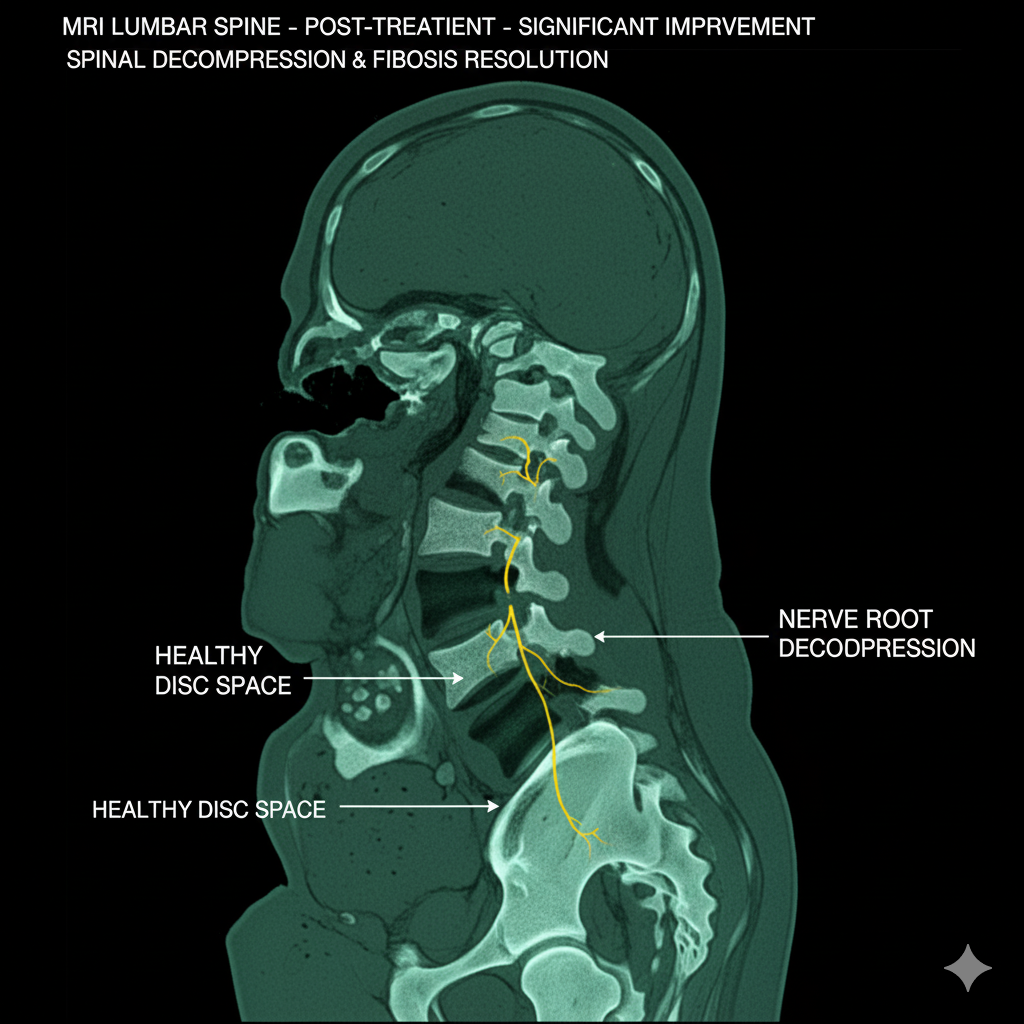

This Is What My Lower Back Look Like Now — One Year After Using Hyggear Lower Back Brace

Who knows where I’d be today if I hadn’t met Martha Klein — the woman who told me about this product and, truly, saved my life.